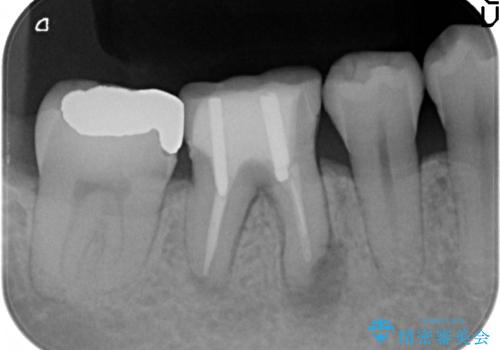

- 数年前から歯茎から膿が出る、治療してもよくならないので診て欲しいといらっしゃった方の症例です。

再根管治療を行い膿の出口の消失及び根尖病変の縮小を確認後、オールセラミッククラウンによる補綴を行いました。